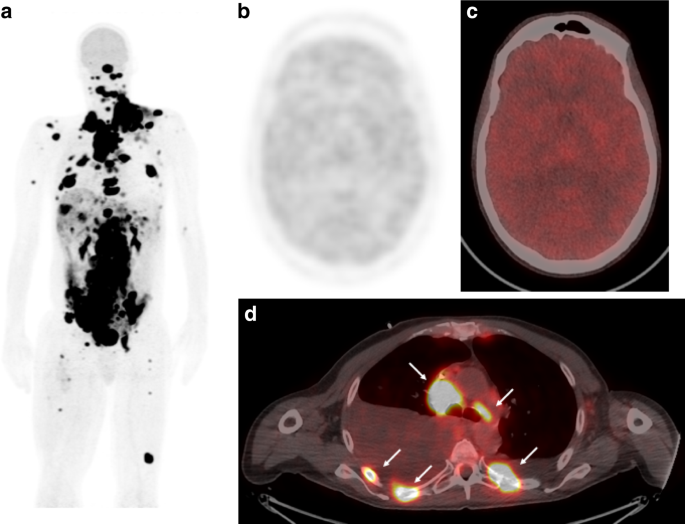

Warburg effect คือ 1 ในคุณสมบัติสำคัญของมะเร็ง(hallmark of cancer) ซึ่ง Dr. Otto Warburg ได้ศึกษายีสต์ที่มีคุณสมบัติเหมือนมะเร็ง และเค้าพบว่ามะเร็งมีปรากฏการณ์นึงที่แตกต่างไปจากเซลล์ปกติคือ เซลล์เร็งมีอัตราการ Glycolysis หรือสลายกลูโคสมาเป็นพลังงานโดยไม่ใช้ oxygen มากกว่าเซลล์ปกติถึง 70-200 เท่า โดยมีสมมติฐานจากไมโตคอนเดรียไม่มีคุณภาพพอ และมีการทำงานของประตูรับกลูโคสเข้าเซลล์มะเร็งที่มากผิดปกติ